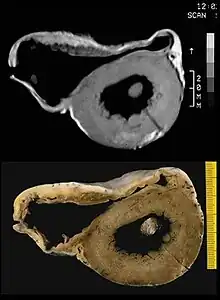

There are two pathological patterns seen in ACM, Fatty infiltration and fibro-fatty infiltration.

Fatty infiltration

At first, fatty infiltration, is confined to the right ventricle. This involves a partial or near-complete substitution of myocardium with fatty tissue without wall thinning. It involves predominantly the apical and infundibular regions of the RV. The left ventricle and ventricular septum are usually spared. No inflammatory infiltrates are seen in fatty infiltration. There is evidence of myocyte (myocardial cell) degeneration and death seen in 50% of cases of fatty infiltration.

Fibro-fatty infiltration

The second, fibro-fatty infiltration, involves replacement of myocytes with fibrofatty tissue. A patchy myocarditis is involved in up to 2/3 of cases, with inflammatory infiltrates (mostly T cells) seen on microscopy. Myocardial atrophy is due to injury and apoptosis. This leads to thinning of the RV free wall (to < 3 mm thickness) Myocytes are replaced with fibrofatty tissue. The regions preferentially involved include the RV inflow tract, the RV outflow tract, and the RV apex. However, the LV free wall may be involved in some cases. Involvement of the ventricular septum is rare. The areas involved are prone to aneurysm formation.

A biopsy sample that is consistent with ACM would have > 3% fat, >40% fibrous tissue, and <45% myocytes.

A post mortem histological demonstration of full thickness substitution of the RV myocardium by fatty or fibro-fatty tissue is consistent with ACM.